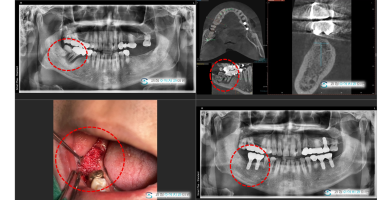

임플란트

다수의 치아를 발치해야하는 상태로 사용할 수 없게된 치아를 발치하고 임플란트를 식립하여 회복한 사례입니다.